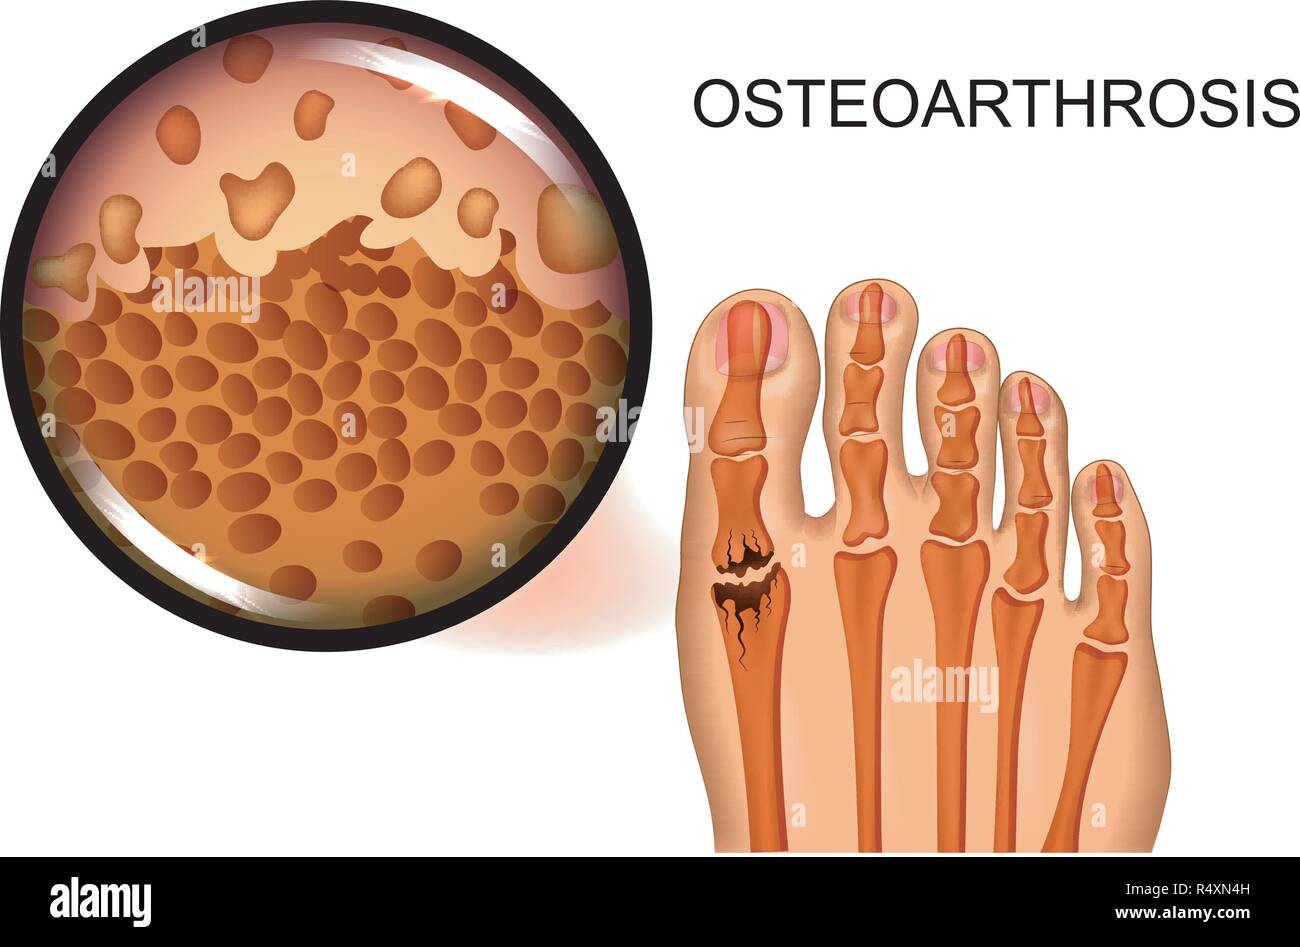

RF2DGMY46–Les verrues du pied sont causées par une infection par un type de virus du papillome humain. Gros plan du HPV

RF2BEFC7R–Douleur au pied et aux jambes. Arthrite et rhumatisme diagramme vectoriel médical orthopédique. Illustration de l'articulation des jambes rhumatismales

RFPKYHHM–La déformation du pied en tant que maladie médicale infographie. Causes de l'oignon. Vector illustration

RFPKYHRK–La déformation du pied en tant que maladie médicale infographie. Causes de l'oignon. Vector illustration